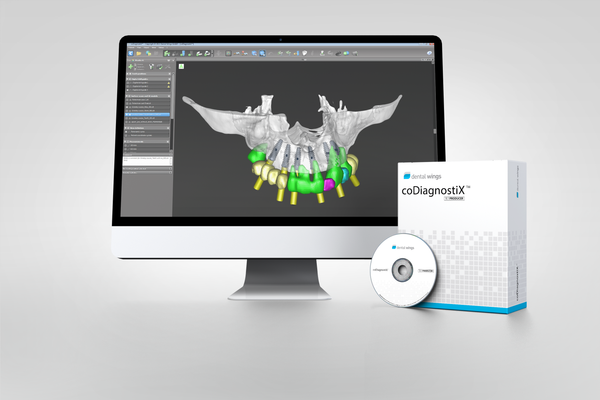

CoDiagnostix® Software - Producer License by Dental Wings

CoDiagnostix® Software - Producer License by Dental Wings

With coDiagnostiX® by Dental wings, you can plan dental implant insertions precisely and easily. It also helps you to design drill guides to perform implant surgery in a fast, precise, and safe manner with predictable results.

The producer license allows for the export of designed Surgical Guides as STL files for 3D printing.

coDiagnostiX® is distinguished by numerous measurement and planning functions, an implant database covering many well-known manufacturers, and precise analyzing capabilities.